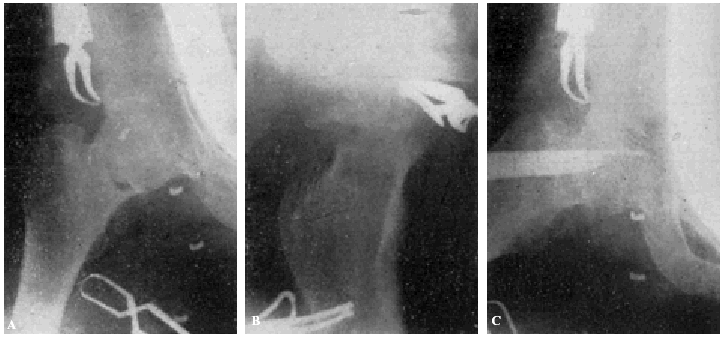

Fracaso número 3(observación número 7). Carmen J., sesenta años. A los cincuenta y tres días de presentar una fractura transcervical del cuello del fémur intentamos el enclavijamiento, que no pudimos realizar por no funcionar los rayos X a causa de una avería eléctrica. No pudimos repetir la intervención hasta pasados veinticuatro días, resultándonos entonces imposible reducir correctamente la fractura (fig. 5., A y B). Enclavijamiento (fig. 5. C) técnicamente defectuoso. A los cuatro meses a causa de presentar una supuración en la herida ingresa nuevamente en el servicio. Una radiografía practicada la misma tarde demuestra la ascensión del clavo, el cual está a punto de perforar el borde superior de la cabeza. Un mes después se extrae dicho clavo. La radiografía parece demostrar una ausencia de consolidación. La enferma deambulaba relativamente bien con ayuda de un bastón.

Figura 5. A: obs. núm. 7. En esta proyección la reducción es, aparentemente, buena; sin embargo, la zona clara que existe a nivel de la línea de fractura, demuestra la ausencia de reducción. B: obs. núm. 7. La fractura no está reducida. C: observación núm. 7. El clavo ha sido colocado de-masiado cranealmente.

La causa fundamental del fracaso en esta observación reside en no haber reducido correctamente la fractura, cosa que hubiéramos conseguido con toda probabilidad gracias a una tracción continua mediante un Kirschner colocado en la metáfisis femoral inferior.